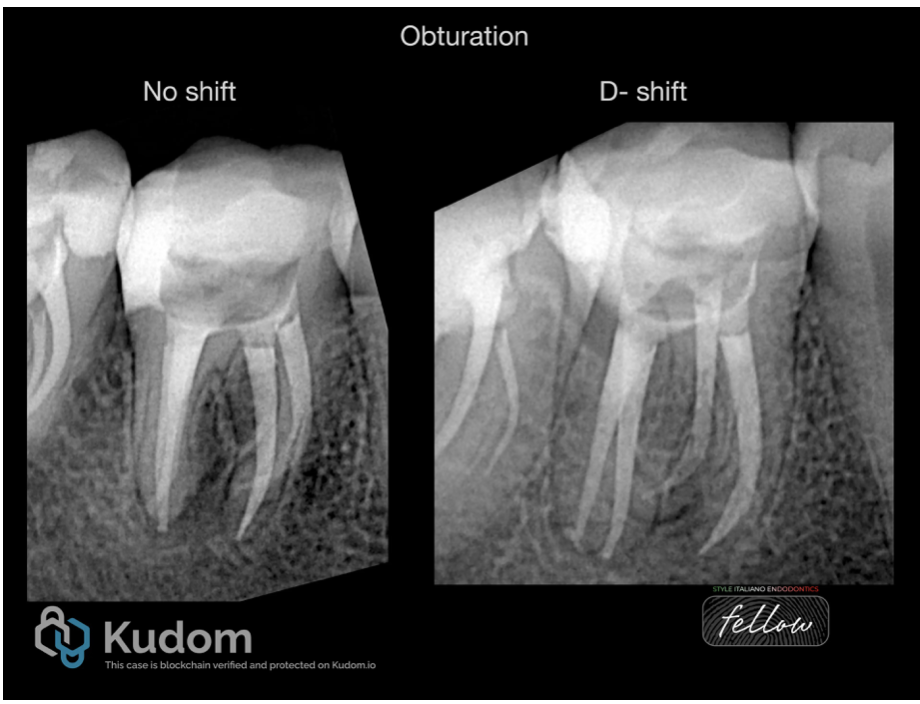

Fig. 7

Obturation done in the same visit. The image shows different shifts .